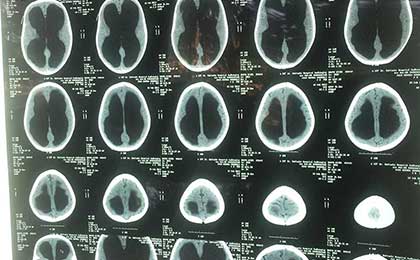

Pre OP CT

PRE OP CT 2